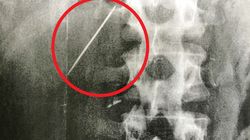

Witam, Moja żona połknęła kawałek szkła. Był on wielkości max 1 cm. Nie wiemy dokładnie, wnioskujemy po ubytku na butelce. Byliśmy u lekarza chirurga bo godzinę po fakcie nastąpiło krwawienie. Stwierdził że jest na razie ok i należy poczekać na wydalenie. Później było już ok. Byliśmy na drugiej konsultacji. Dostaliśmy podobną odpowiedz. Aktualnie mija 8 dni od połknięcia. Kiedy możemy być w miarę pewni że już jest po wszystkim?

Należy przypuszczać , że szkło opuściło już przewód pokarmowy , ale to nigdy nie jest do końca pewne! Szkoda , że Żona nie prowadziła b.dokładnej kontroli wydalanego stolca (np. na pampersa) - byłoby pewne czy szkło zostało wydalone , czy nie! zż